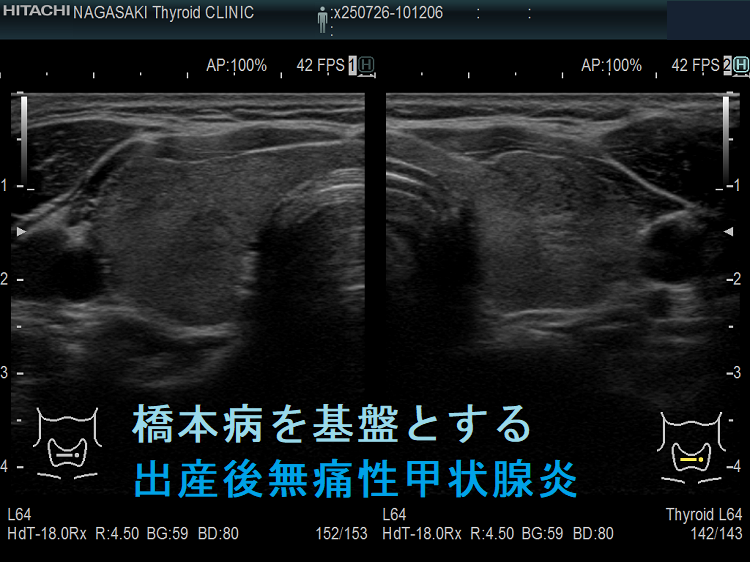

出産後無痛性甲状腺炎 超音波(エコー)画像;下甲状腺動脈の収縮期最大血流速度(ITA-PSV)

無痛性甲状腺炎であるため、下甲状腺動脈の収縮期最大血流速度(ITA-PSV)は低値です。

橋本病を基盤とする出産後無痛性甲状腺炎(水平断) ドプラーモード;無痛性甲状腺炎であるため、内部血流は少ない。

橋本病を基盤とする出産後無痛性甲状腺炎下甲状腺動脈の収縮期最大血流速度(ITA-PSV);無痛性甲状腺炎であるため、下甲状腺動脈の収縮期最大血流速度(ITA-PSV)は低値